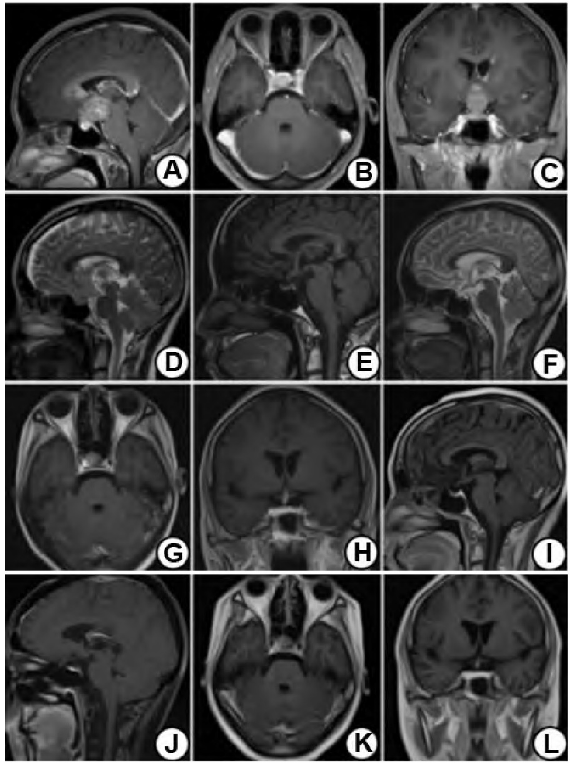

入院颅脑MRI平扫及增强显示:鞍上、左侧丘脑、侧脑室壁及基底节区内异常信号影,较大的范围约28 mm×24mm,边界尚清楚,形态欠规整,呈稍短T1、稍长T2信号,其内见结节状长T2信号影;增强扫描呈不均匀强化,病灶与垂体分界不清楚,垂体柄显示不清楚(图1A~C)。

钠治疗。术后10 d,垂体MRI显示:鞍上不规则团块状异常信号影,呈等T1、等/稍长T2信号影,信号欠均,边界较清楚(图1D)。

术后第6周开始“全脑+全脊髓”普通放射治疗,DT 30 Gy×15次(5次/周)。随后开始“全脑加量”普通放射治疗,DT 24 Gy×12次(5次/周)。放疗至DT 46Gy×23次后复查头颅MRI显示:鞍上占位较前明显缩小(图1 E~H)。

甲状腺氨酸0.53 nmol/L,甲状腺素39.10 nmol/L,游离三碘甲状原氨酸1.50 pmol/L,游离甲状腺素4.59 pmol/L。放射治疗完成后3个月,复查MRI,鞍区未见明显结节、肿块影(图1I~L);复查性激素六项中泌乳素为1536.00 IU/L,其余激素水平仍低于正常值;另外,血清游离甲状腺素水平为8.44pmol/L。病人继续醋酸泼尼松及左甲状腺素钠替代治疗,但月经仍未恢复。

图1 颅内原发无性细胞瘤伴继发性闭经病人手术前后及放疗后影像表现。A~C.术前MRI增强见鞍上较大异常信号影,呈不均匀强化,病灶与垂体分界不清;D.术后10 d复查MRI示鞍上术后改变,鞍上见不规则团块状异常信号影,呈等T1、等/稍长T2信号影,信号欠均,边界较清,大小约26 mm×28mm×36 mm;E~H.放疗至DT 46 Gy×23次后复查MRI示鞍上占位明显缩小;I~L.放疗完成后3个月复查MRI示鞍区未见明显结节、肿块影,垂体局部强化信号欠均